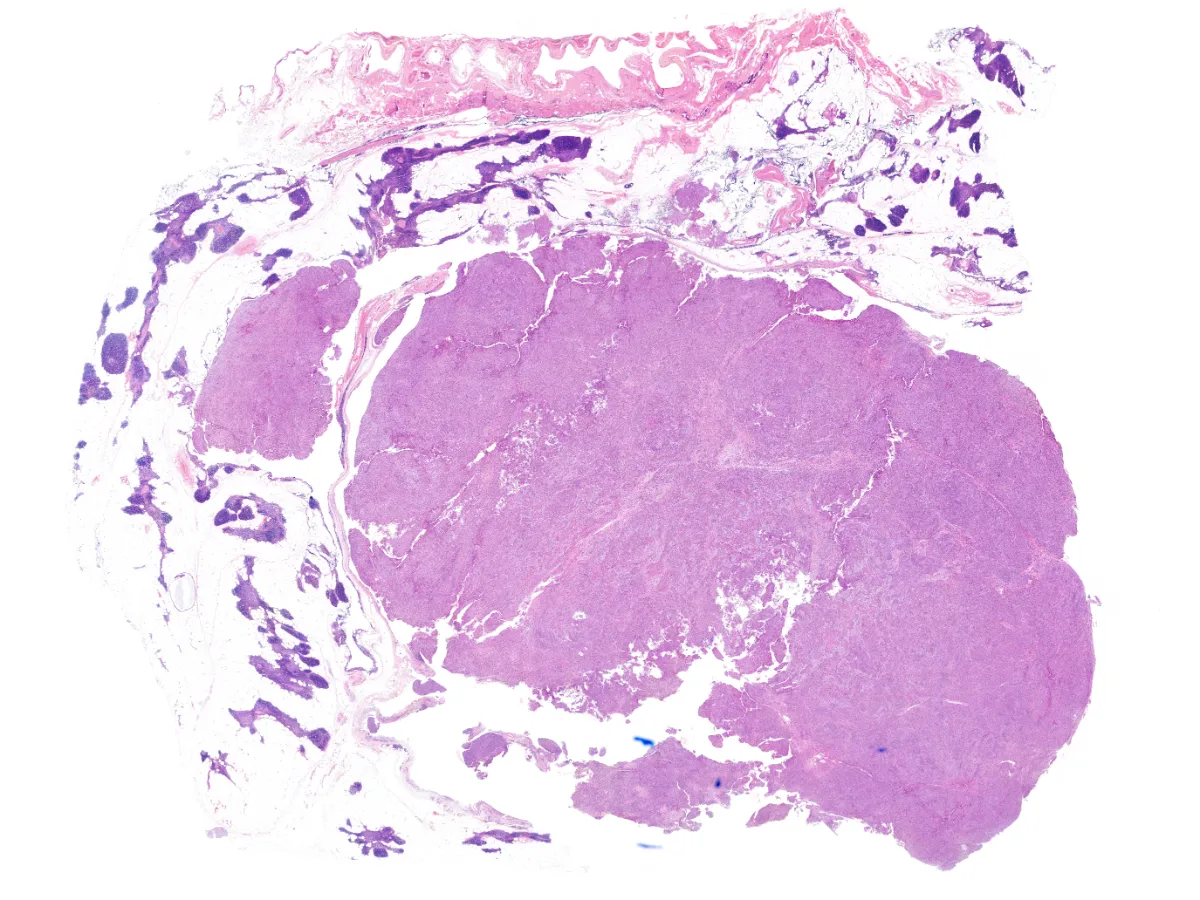

1. HE 1x

Diagnóstico: Timoma metaplásico

- Se trata de un tumor bifásico de origen tímico compuesto por islas de células epiteliales y células fusiformes de bajo grado citológico, con áreas de transición de gradual a abrupta entre ambos componentes.